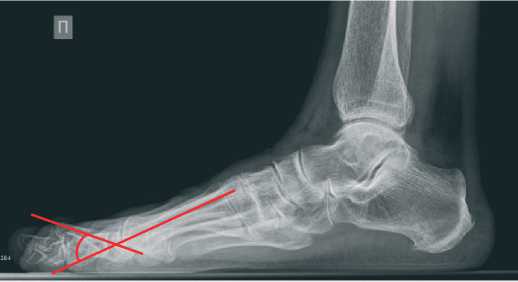

По данным стандартной рентгенографии стопы угол hallux valgus (М1Р1) исходно равен 45 градусов (Рисунок 2), угол ТО второго пальца – 45 градусов (Рисунок 3).

Рисунок 3. Исходные данные рентгенографии правой стопы в боковой проекции

По рентгенограмме в прямой проекции было подтверждено полное устранение hallux valgus (угол М1Р1= 7 градусов) (Рисунок 5). На снимке в боковой проекции угол ТО был равен 30 градусов (Рисунок 6).

Рисунок 6. Данные рентгенографии правой стопы в боковой проекции через 1 год после операции